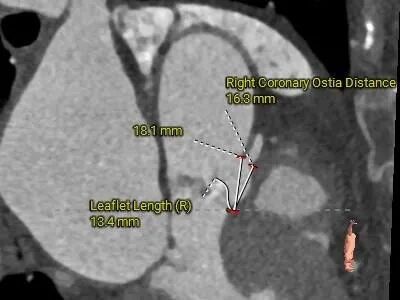

• 左、右冠高度可,切线位测量,左窦瓣叶稍长于左冠开口下缘;左主干及前降支可见部分钙化斑块;

冠脉评估

• 左、右冠高度可,切线位测量,左窦瓣叶稍长于左冠开口下缘,结合瓦氏窦、STJ内径综合预估,冠脉阻挡风险适中,术中在瓣膜释放至工作位后进一步观察冠脉灌注情况;